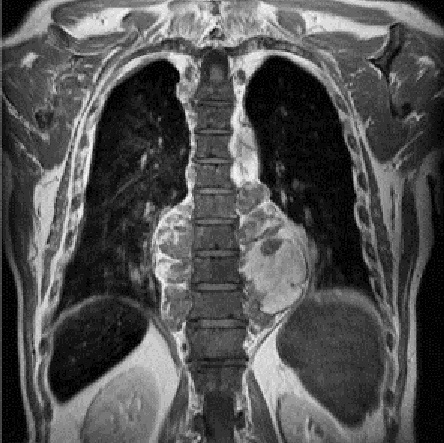

Même cas en coupe coronal IRM

ponderee sur T2 mettaient en évidence une masse para

vertébrale bilatérale hétérogène et volumineuse . Le

diagnostic est tumeur hematopoiese extra-medulaire

. Image radiologique IRM thoracique en coupe coronal

pondérée sur T2. |